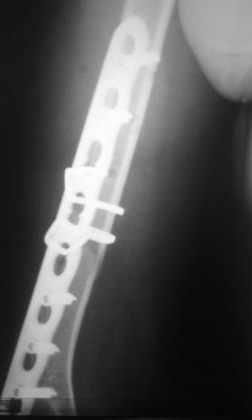

Re: Перелом н\3 плечевой кости. Тактика лечения?

Перелом нестабильный, тактика - если позволяет сосояние больной, оперативное лечение. Как пример см. ниже, можно без скобы - стяжки с ЭПФ.

Представленный способ, функциональный, данная больная в качестве внешней иммобиллизации в течение 3-х недель полльзовалась косыночной повязкой, востановление функции плеча полное. Правда травма изолированная, но операция выполнялась через три недели после травмы, тот час после обращения ко мне - иногородняя.